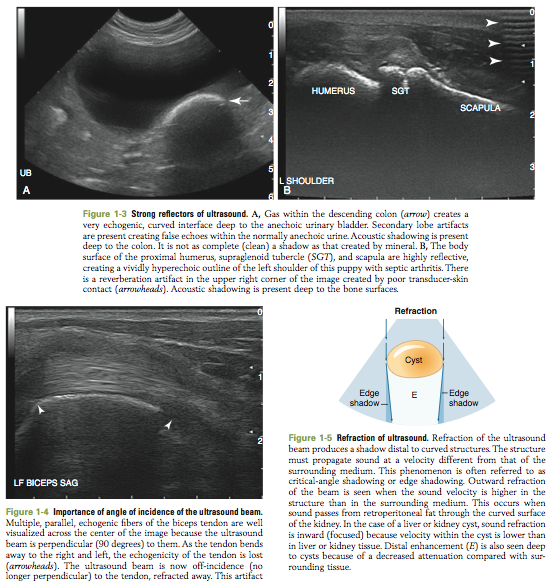

Fundamentals of Diagnostic Ultrasound